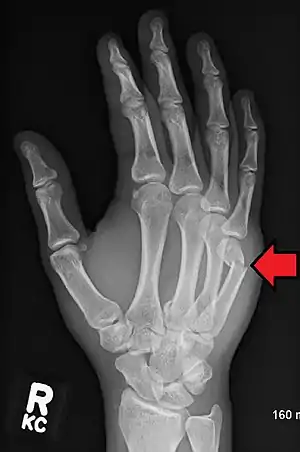

A boxer's fracture is the break of the 5th metacarpal bones of the hand near the knuckle.[4] Occasionally it is used to refer to fractures of the 4th metacarpal as well.[1] Symptoms include pain and a depressed knuckle.[2]

| Boxer's fracture of the 5th metacarpal head from punching a wall | |

Classically, it occurs after a person hits an object with a closed fist.[3] The knuckle is then bent towards the palm of the hand.[3] Diagnosis is generally suspected based on symptoms and confirmed with X-rays.[3]

Diagnosis by a doctor's examination is the most common, often confirmed by x-rays. X-ray is used to display the fracture and the angulations of the fracture. A CT scan may be done in very rare cases to provide a more detailed picture.